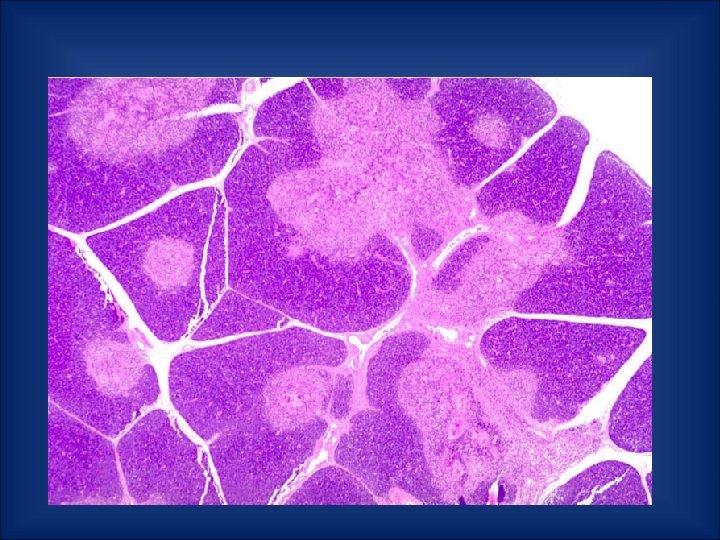

Spleen • Upper left quadrant of the abdomen • Not a vital organ • Surrounded by a fibrous capsule • Composed of red and white pulp

Structure of spleen • Red pulp 1. sinuses – vessel-like spaces filled with blood 2. splenic cords – reticular fibers 3. marginal zone bordering on white pulp • White pulp - nodules - Malpighian corpuscles 1. follicles - rich in B-lymphocytes 2. periarteriolar lymphoid sheath - T-lymphocytes